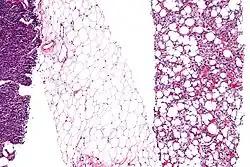

Micrograph showing some dedifferentiation, (at left edge of image). + A differentiated component, showing lipoblasts and increased vascularity, (right edge of image). + Fully differentiated adipose tissue, showing a few blood vessels, (center of image). (Micrograph of liposarcoma prepared with H&E stain).

Dedifferentiation, or integration, is a cellular process seen in the more basal life forms in animals, such as worms and amphibians where a differentiated cell reverts to an earlier developmental stage—usually as part of a regenerative process.[18][19] Dedifferentiation also occurs in plant cells.[20] And, in cell culture in the laboratory, cells can change shape or may lose specific properties such as protein expression—which processes are also termed dedifferentiation.[21]